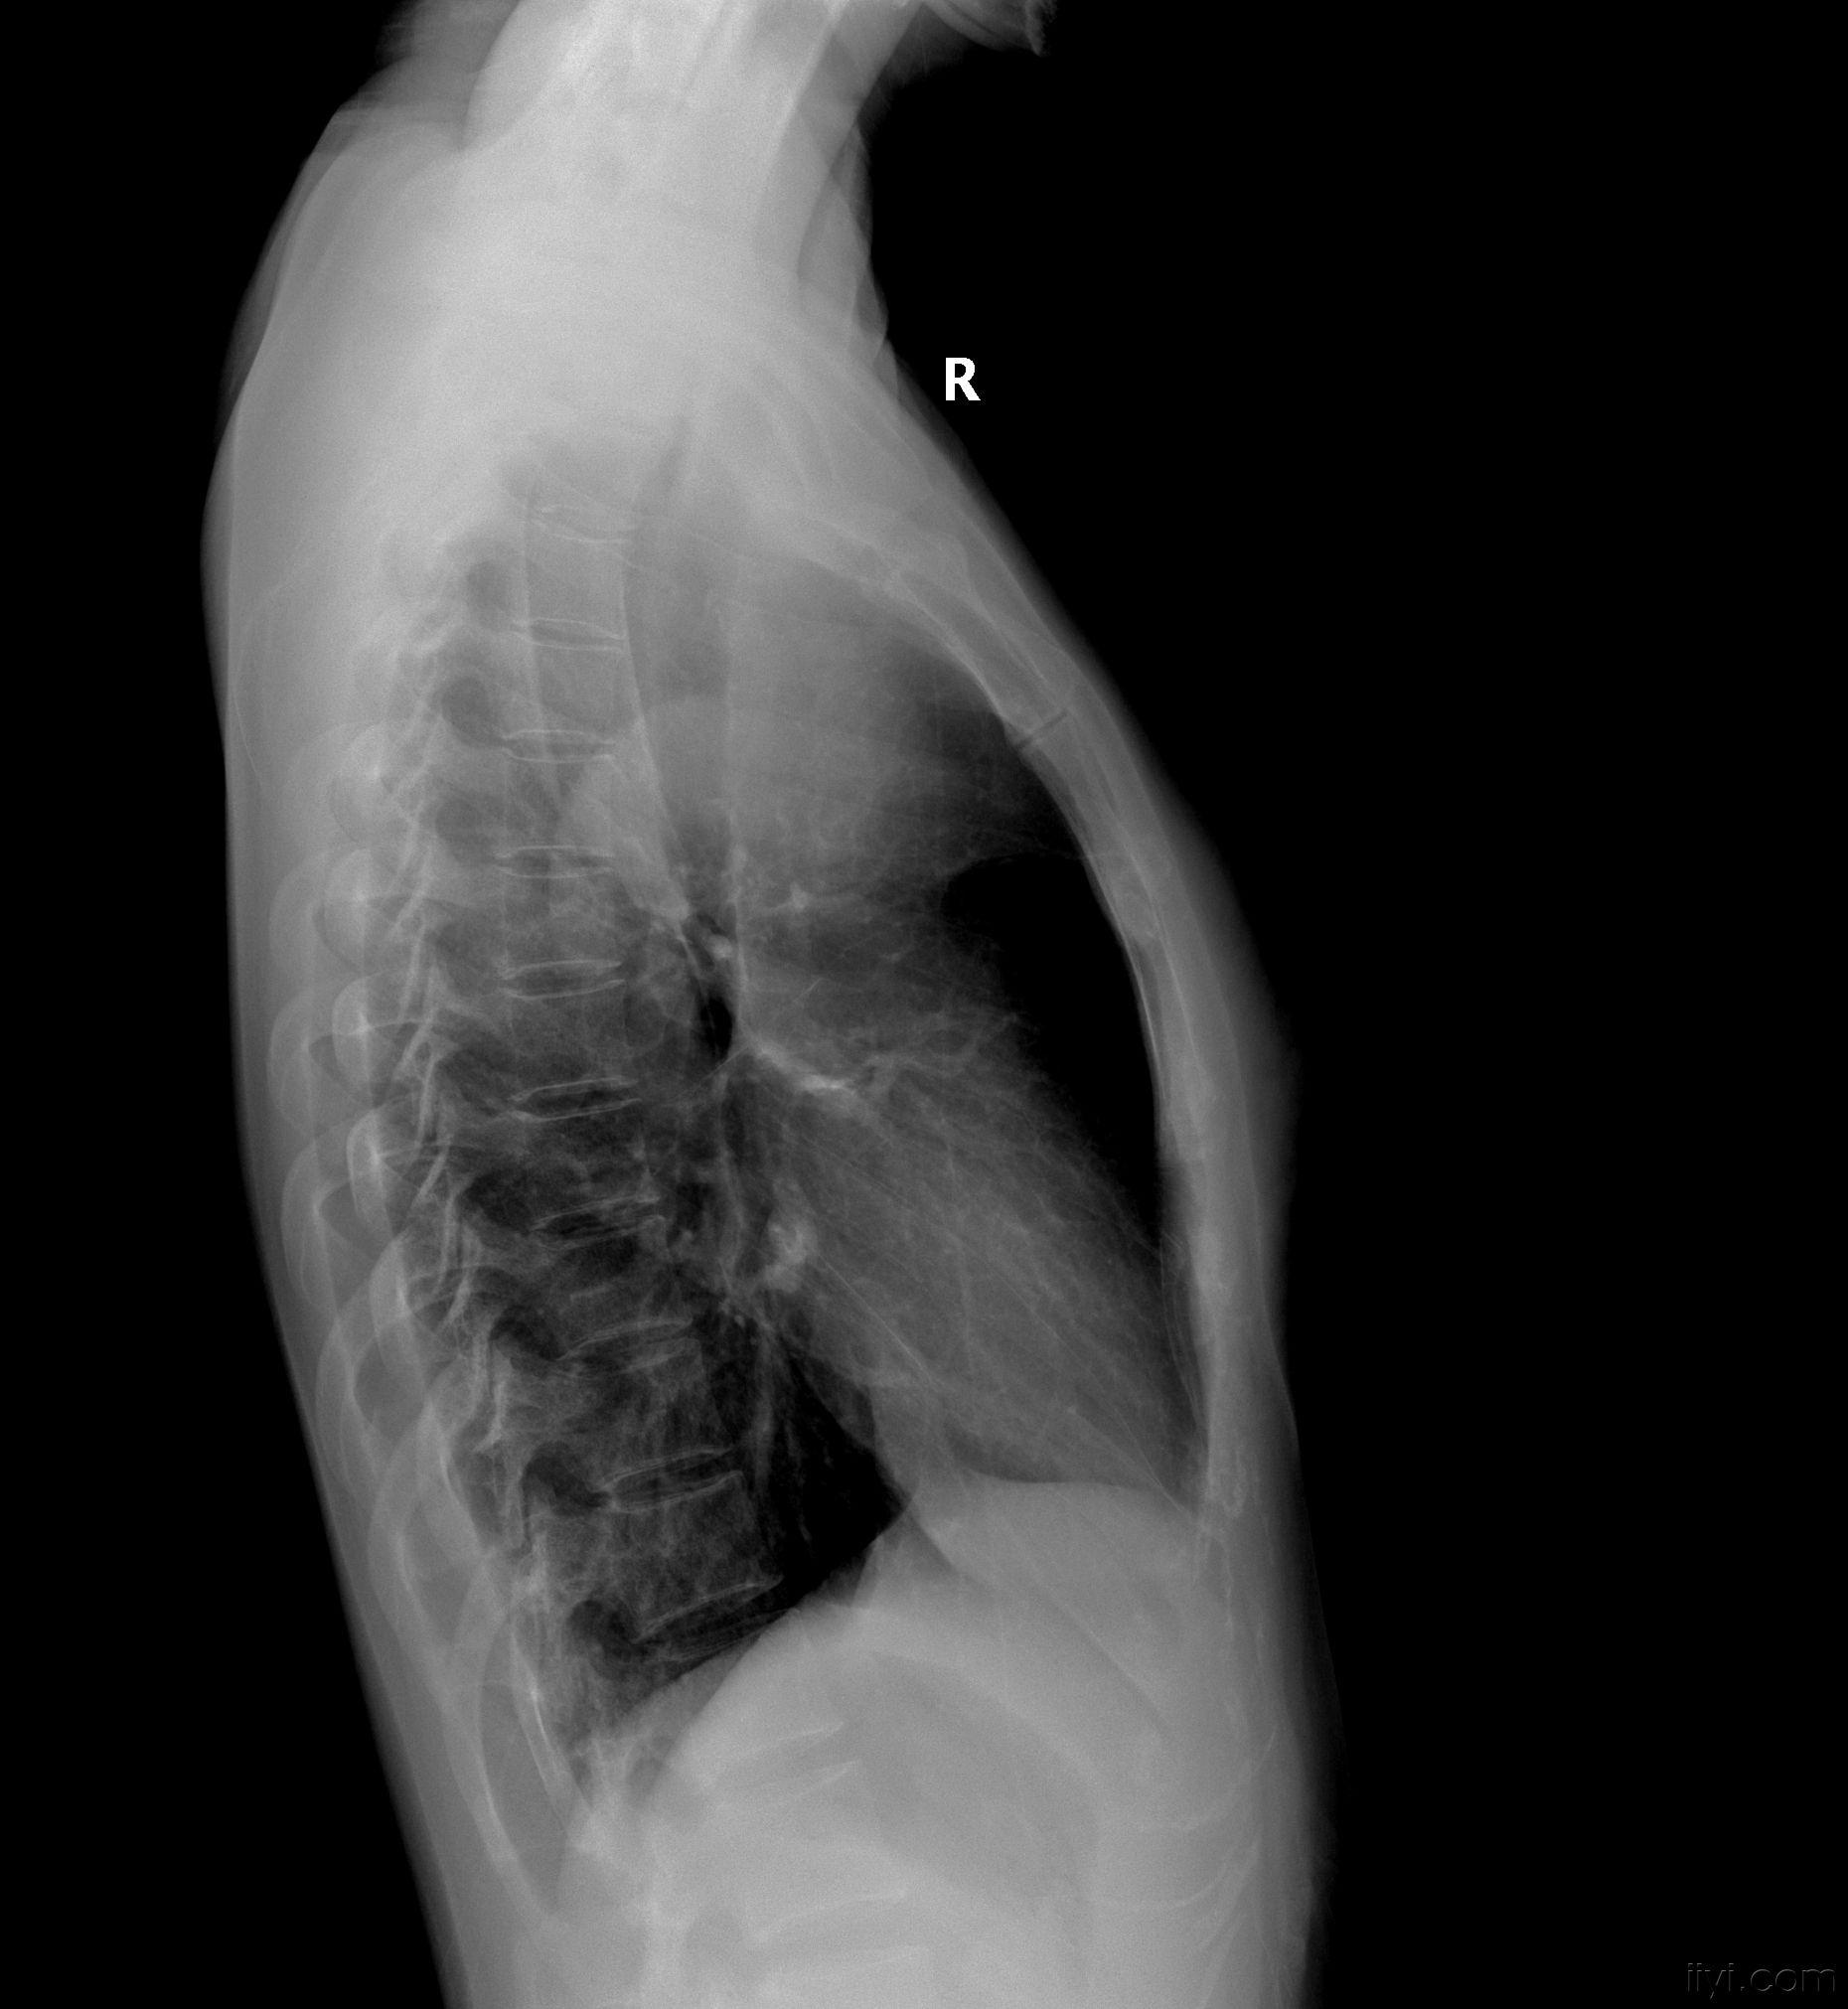

少见病例,大家看看象啥.(已经公布病理: 胸内甲状腺肿)

胸内甲状腺肿(22213985)